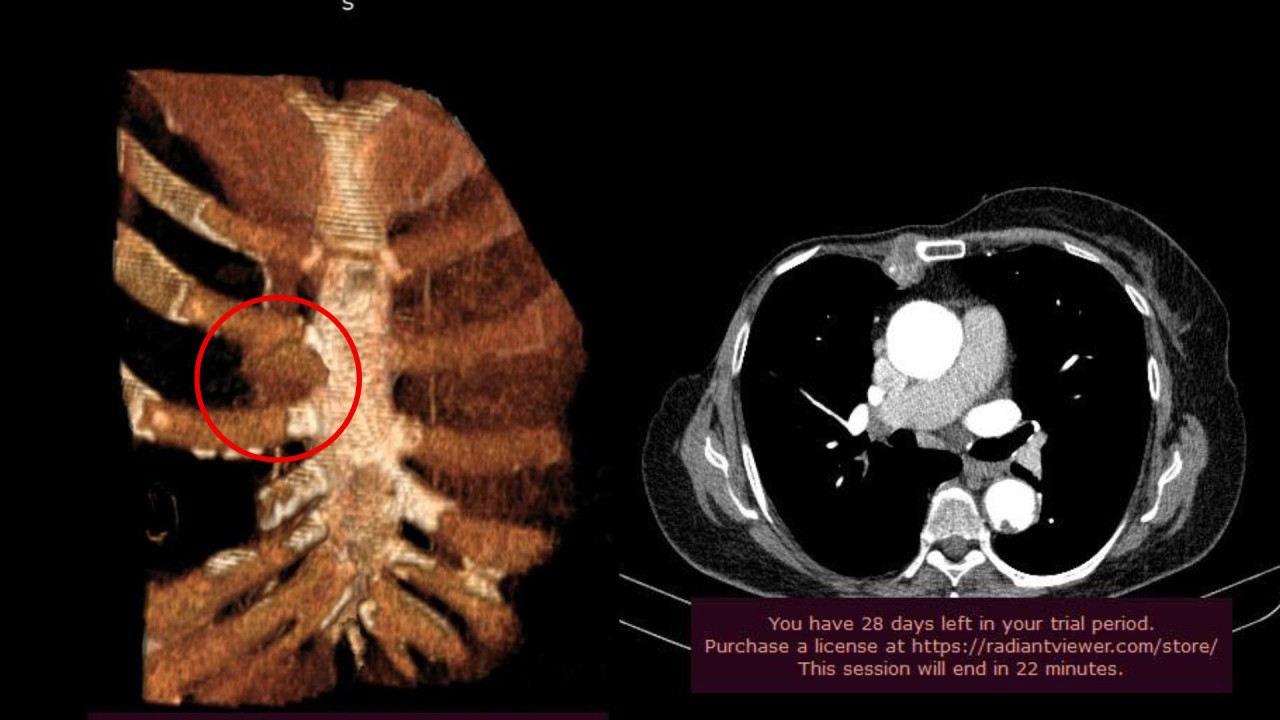

Այցի շրջանակում պրոֆեսոր Ուոնգը և ՈՒԱԿ Կրծքավանդակային վիրաբուժության և ինտերվենցիոն թոքաբանության բաժանմունքի վարիչ, թորակալ վիրաբույժ Տիգրան Բյուզանդյանը կատարել են համատեղ վիրահատական միջամտություն՝ կրծքավանդակի պատի մասնատում` 2-րդ, 3-րդ և 4-րդ կողոսկրերի  և կրծոսկրի մասնահատումով, ուռուցքի հեռացումով, պլաստիկայով։